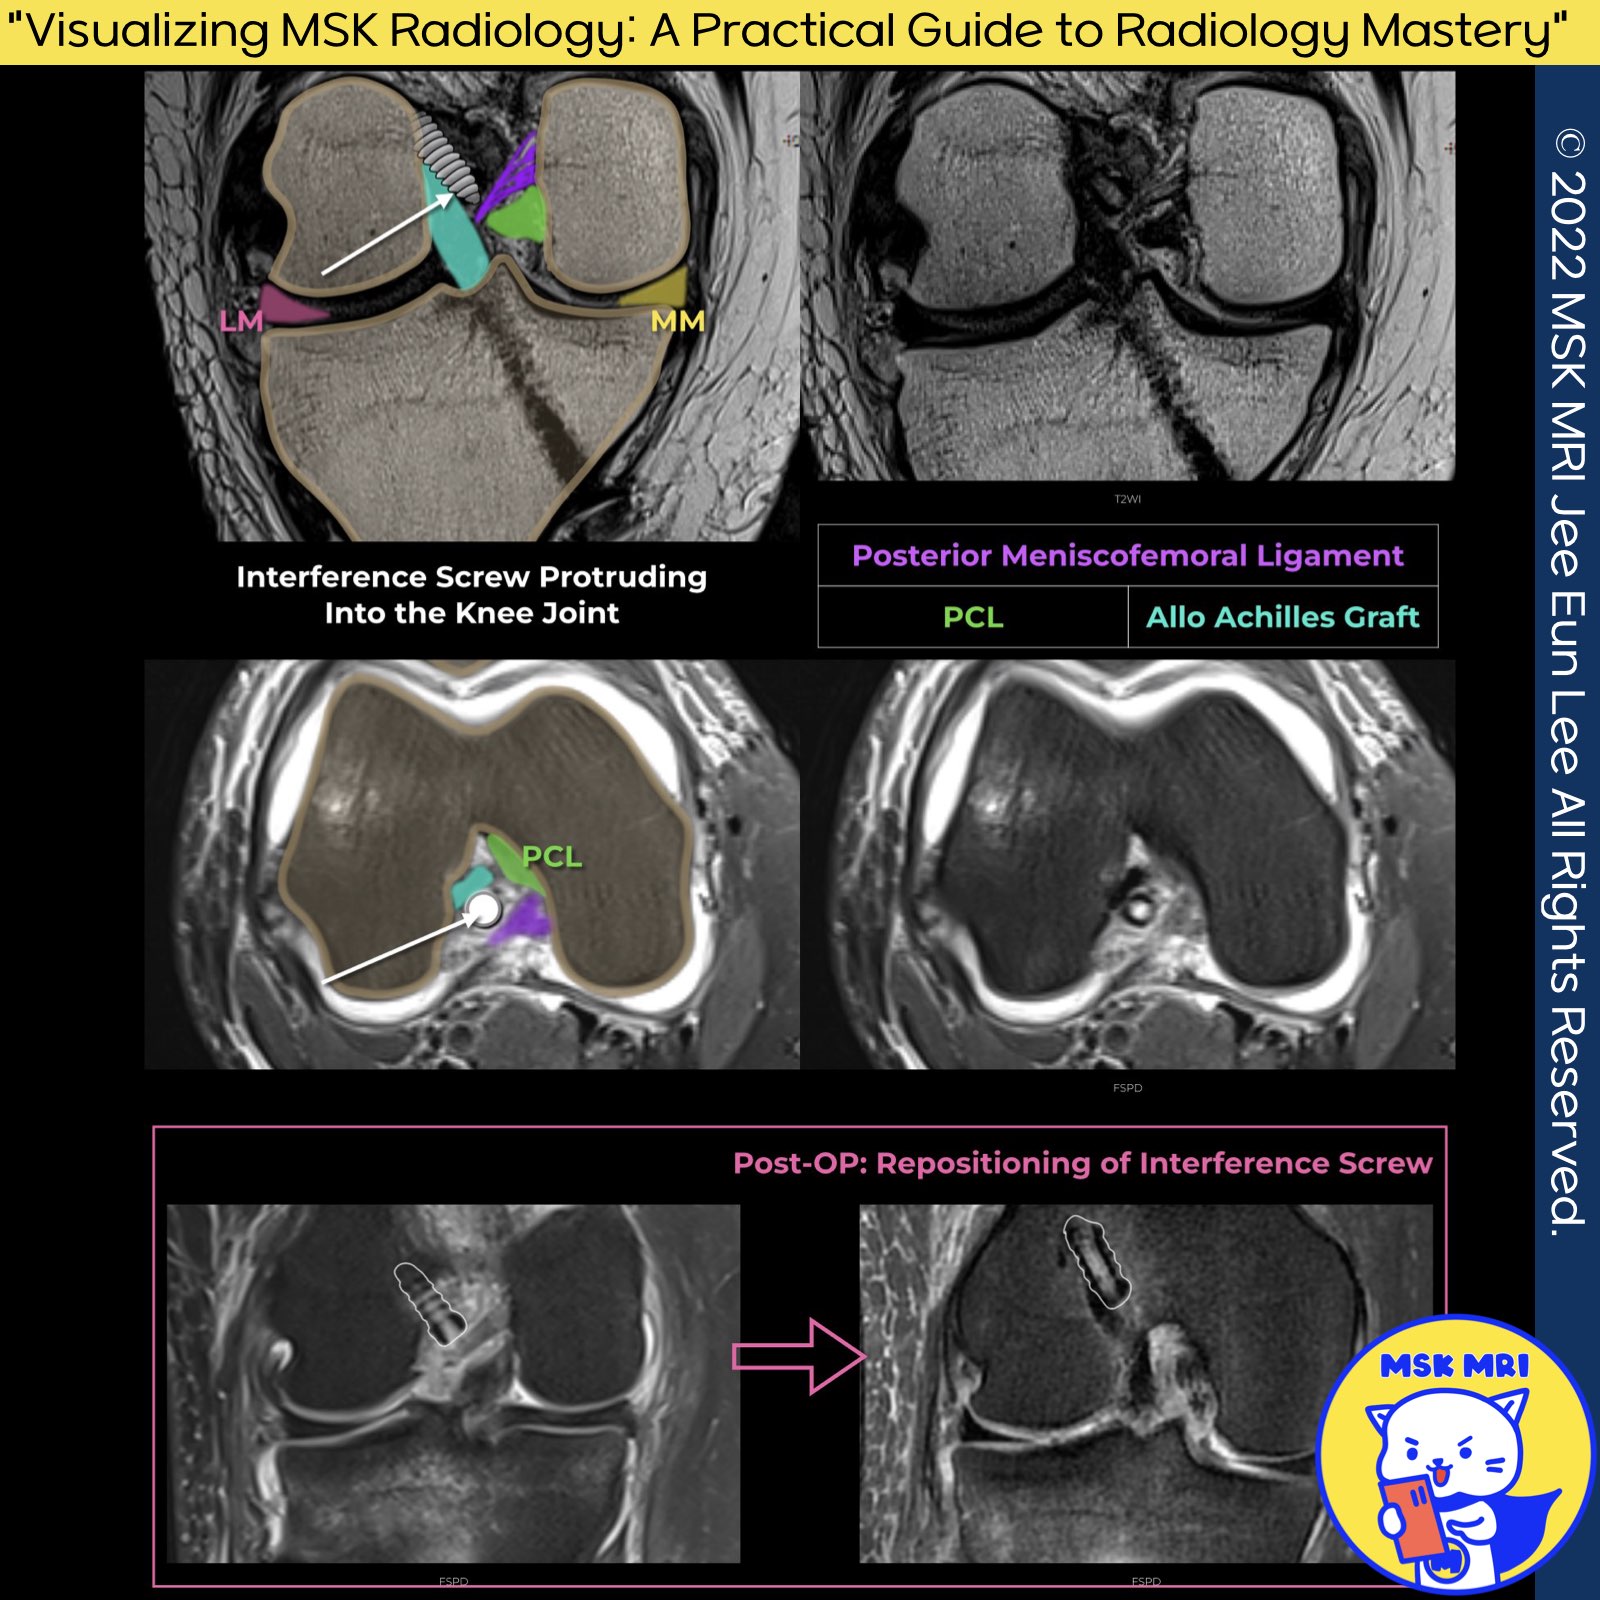

1️⃣ Types of Hardware Failure

- Hardware fracture

- Dislodgement

- Malpositioning

2️⃣ Consequences of Hardware Failure

- Mechanical symptoms from fractured or dislodged hardware

- Graft fixation failure if hardware fails before graft incorporation

- Mechanical impingement or irritation from malpositioned or displaced hardware fragments

Magn Reson Imaging Clin N Am. 2022 May;30(2):261-275